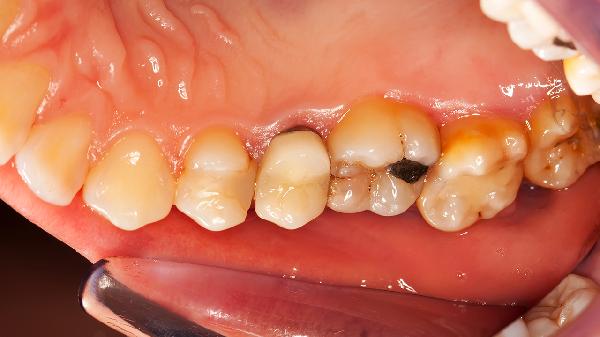

尿酸結(jié)晶沉積在關(guān)節(jié)引發(fā)炎癥,常因高嘌呤飲食誘發(fā)。大腳趾關(guān)節(jié)突發(fā)劇痛伴皮膚發(fā)亮是典型表現(xiàn)。發(fā)作期需用秋水仙堿片、非布司他片控制癥狀,配合苯溴馬隆片調(diào)節(jié)尿酸。患者需嚴格限制動物內(nèi)臟攝入,每日飲水保持2000毫升以上。